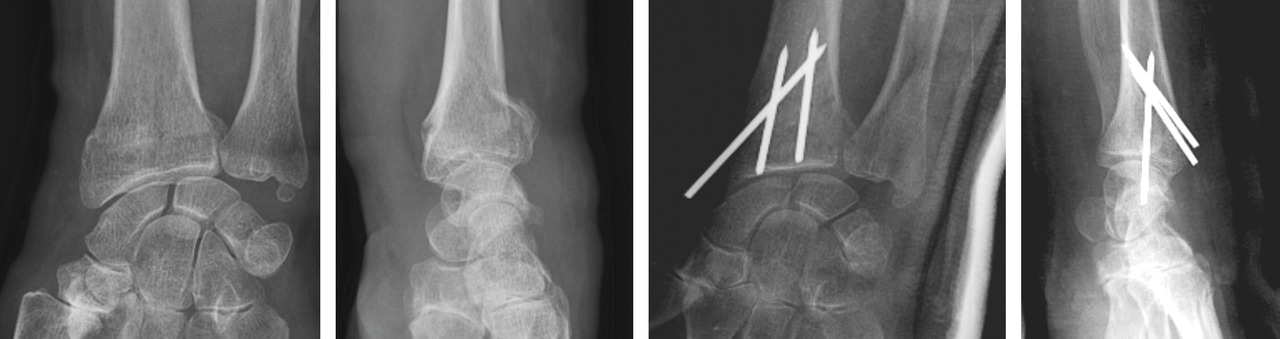

Le traitement chirurgical, justifié en cas de déplacement non tolérable, repose sur 3 modalités pratiques distinctes : l’embrochage percutané, les plaques palmaires vissées, et le fixateur externe radiométacarpien, à ne jamais utiliser seul. Ces traitements remplissent le double rôle de réduction et de stabilisation de la fracture jusqu’à consolidation.

La mise en place des broches percutanées sont habituellement introduites dans le foyer de fracture, en arrière du radius, puis inclinées vers le bas pour réduire la bascule dorsale de la glène radiale et sont finalement fichées dans la corticale antérieure, épaisse, pour stabiliser la réduction obtenue. Il s’agit d’un embrochage « intrafocal » (dans le foyer de fracture). Une ou deux broches styloïdiennes dans le plan frontal complètent le montage. La bascule antérieure du fragment distal, la présence de refends articulaires, et la comminution métaphyso-épiphysaire sont indispensables à évaluer avant de proposer ce type de traitement et constituent des contre-indications relatives (fig. 12).

La mise en place de plaques palmaires nécessite un abord chirurgical antérieur et reste techniquement délicat, en particulier pour positionner la plaque en hauteur et pour la longueur des vis dont l’excès peut endommager les tendons extenseurs. L’indication phare reste les fractures métaphysaires à déplacement antérieur ou les comminutions métaphysaires étendues (fig. 13).

Enfin, le fixateur externe ne doit pas être utilisé seul car une traction excessive est un facteur de risque d’algo­neurodystrophie. Il doit être ajouté comme moyen de protection d’une ostéosynthèse par broche ou plaque précaire. Son rôle est de neutraliser les contraintes en compression sur l’extrémité inférieure du radius en cours de consolidation (fig. 14).